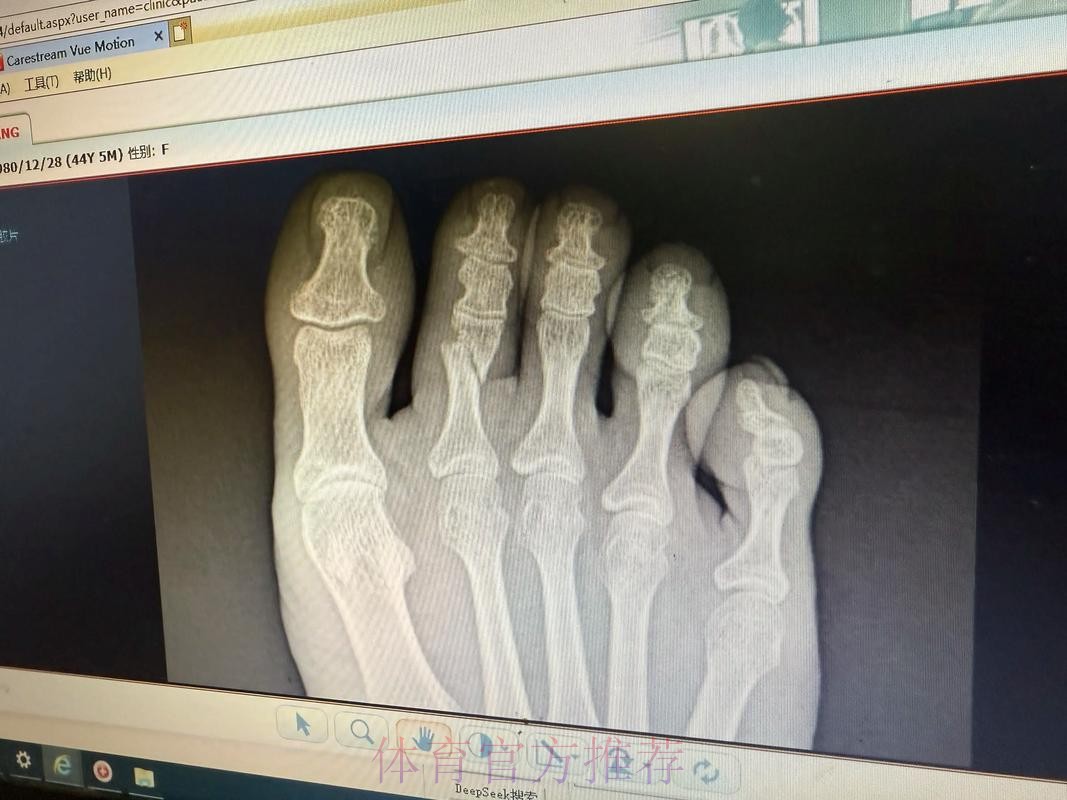

皇马官方-琼阿梅尼左脚第二跖骨不完全应力性骨折

皇马官方伤情通告背后的信号 皇马官方一向在伤病信息上措辞谨慎,但“左脚第二跖骨不完全应力性骨折”这句话本身已经透露出不少关键信息。这是跖骨部位的应力性损伤,而非一次剧烈对抗造成的瞬间骨折,说明问题来自长期负荷积累,是典型的疲劳型伤病。“不完全”意味着骨结构尚未完全断裂,仍保持一定连续性,这对康复时间和方式具有决定性影响。如果处理得当,往往可以通过相对保守的治疗方案避免手术;但一旦急于复出或训练负荷控制不当,就有可能从“不完全”演变为完全性骨折,令缺阵期成倍延长。对于依赖琼阿梅尼在中场完成覆盖和防守平衡的皇家马德里来说,如何在争冠压力下保护好球员、又不让球队竞技水准大幅下滑,将是一场同样艰难的“心理博弈”。

皇马官方:琼阿梅尼左脚第二跖骨不完全应力性骨折

跖骨应力性骨折究竟意味着什么 许多球迷听到“应力性骨折”会下意识以为只是轻微小伤,但在运动医学语境中,这却是对高负荷训练的一种严肃警告。跖骨是足部承重和发力的重要骨骼,足球运动中的短距离爆发、急停变向、频繁起跳落地,都会不断将力量传导至跖骨区域。当训练和比赛的总量超过身体适应阈值,同时恢复时间又不足时,骨组织内部会出现微小裂纹,这些微裂如果得不到及时修复,就逐渐累积形成应力性骨折。不完全应力性骨折通常意味着裂纹尚未贯通骨骼,两侧仍存在结构支撑,因此患者在早期往往还能咬牙坚持训练甚至上场。但正是这种“还能坚持”的错觉,使得应力性骨折在职业足球中极具隐蔽性——当你真正感觉到强烈疼痛时,很可能已经接近完全骨折的边缘。琼阿梅尼的伤情被及时查出,某种程度上说明皇马医疗团队对他的反馈足够重视,也体现了俱乐部在数据监控和身体管理上的专业度。

运动医学视角下的康复和复出节奏 从医学角度看,左脚第二跖骨不完全应力性骨折的康复核心在于“控制负荷”和“逐步恢复”。初期需要通过休息和减压让骨组织完成自我修复,有时会配合使用护靴或拐杖减少足部承重;中期则通过理疗、轻量力量训练和本体感觉训练逐步恢复功能;后期则要加入跑动、变向和带球训练,模拟比赛中的真实对抗场景。真正的难点不在诊断,而在“何时可以回到90分钟高强度比赛”这道关卡。如果皇马在赛程压力或舆论压力下过早安排琼阿梅尼复出,哪怕他在短时间内状态看似良好,也可能埋下复发或二次伤病的隐患。对球员而言,学会倾听身体信号,与医疗团队保持坦诚沟通,避免“硬扛文化”的主导,也是职业生涯能否拉长的重要因素。